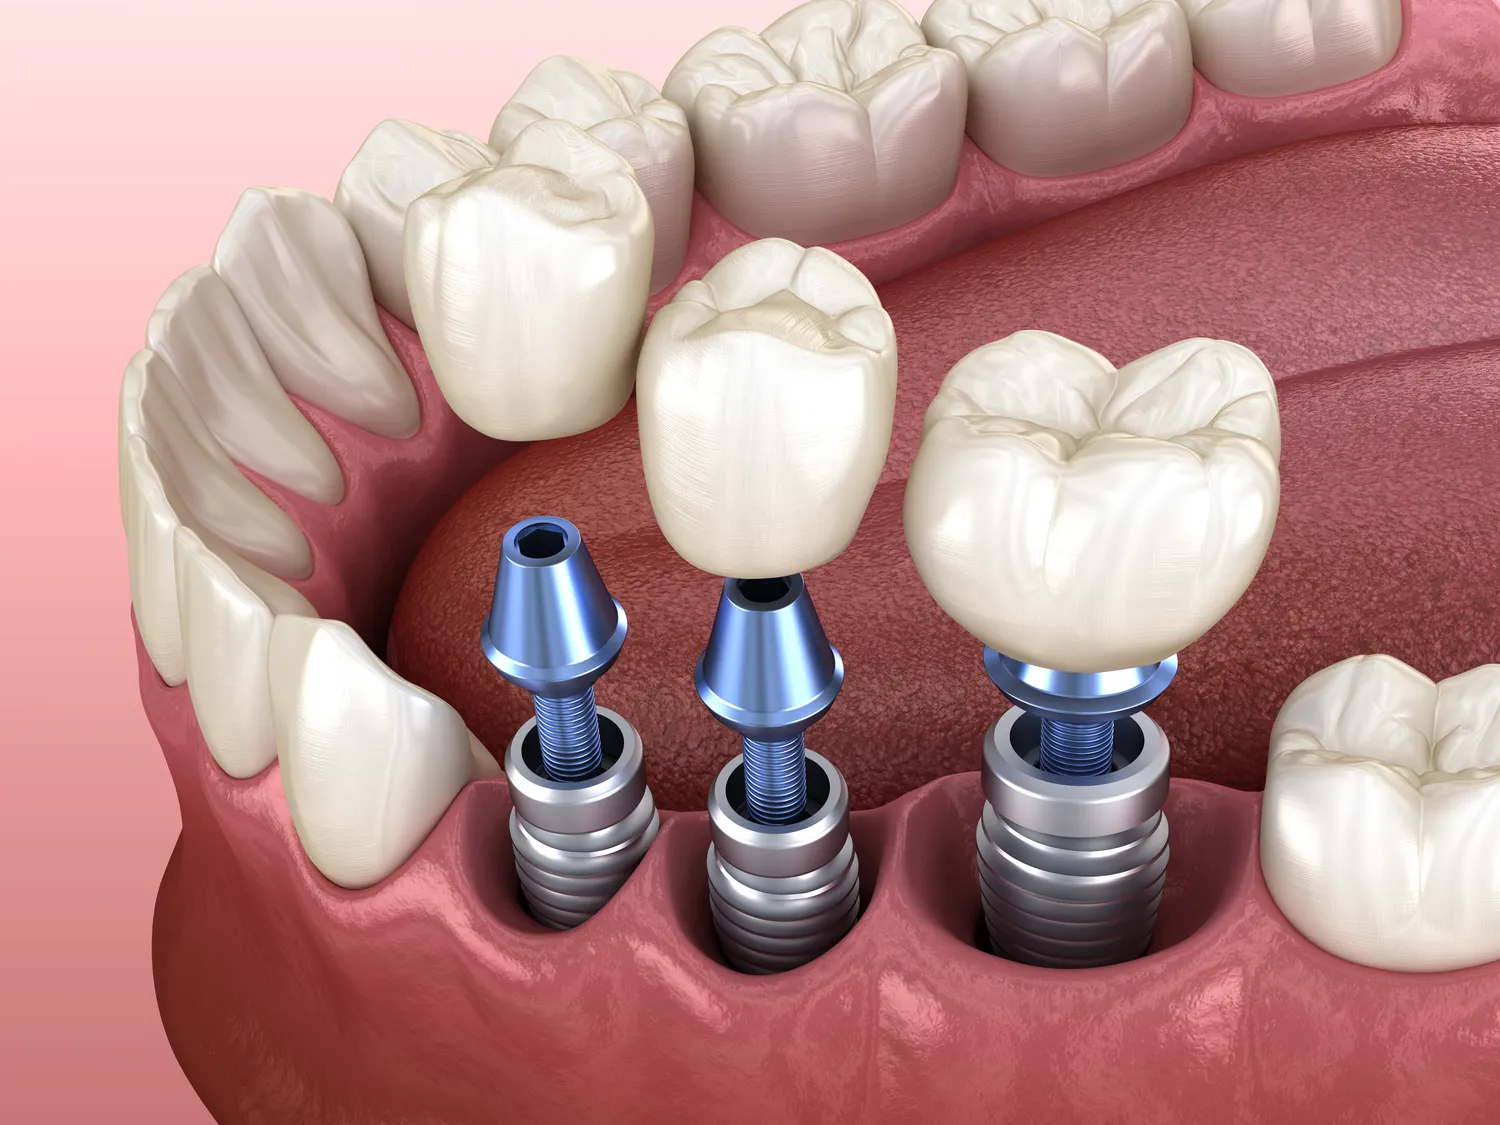

W sytuacjach, gdy leczenie kanałowe nie jest możliwe lub nie przynosi oczekiwanych rezultatów, istnieją alternatywy, które mogą być rozważane przez pacjentów i dentystów. Jedną z najczęściej stosowanych opcji jest ekstrakcja zęba, czyli jego usunięcie. Choć jest to ostateczność i wiąże się z utratą naturalnego uzębienia, czasami może być jedynym rozwiązaniem w przypadku zaawansowanej choroby przyzębia lub ciężkich infekcji. Po ekstrakcji można rozważyć różne metody odbudowy brakującego zęba, takie jak implanty dentystyczne czy mosty protetyczne. Inną opcją są terapie zachowawcze polegające na stosowaniu leków przeciwbólowych i antybiotyków w celu złagodzenia objawów i kontrolowania infekcji bez interwencji chirurgicznej.